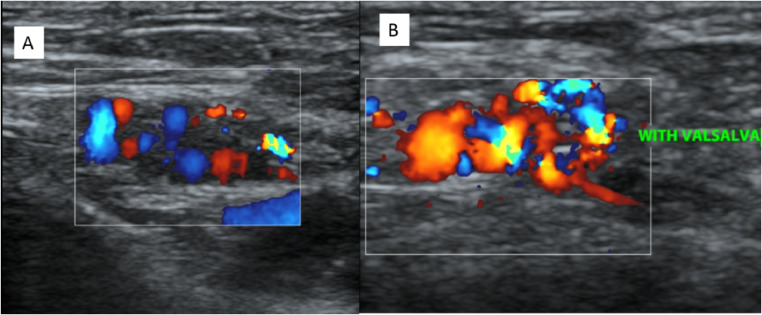

Ultrasound and color Doppler was done with MINDRAY DC-8 machine with 12 Hz probe in which gray-scale sonography showed an asymmetric left inguinal anechoic mass composed of multiple serpentine tubular channels (Fig. 1). Color Doppler imaging showed a hyper vascular structure with a venous flow pattern (Fig. 2) which became more prominent and showed reflux when the patient performed valsalva maneuver (Fig. 3). There were no intraluminal echogenic findings to suggest thrombus formation; there were no soft tissue components, no bowel loops, or lymphadenopathy. A diagnosis of round ligament varices was made and patient was managed conservatively.

Fig. 3.

On color Doppler imaging—(A) in resting phase color filling of channels present (B) with valsalva increase in AP dimension of lesion and reflux of color seen.

RVLs are more common than inguinal hernias and for the diagnosis of RLV, sonographic examination is necessary and sufficient. On ultrasonography, the typical findings of RLV on gray-scale sonography are the “bag of worm” appearance of the subcutaneous tissue which is formed by the multiple dilated veins and its extension through the inguinal canal. On color Doppler imaging, the existence of venous flow and its augmentation by Valsalva manoeuvre confirm the diagnosis [3].